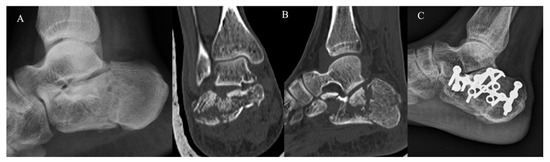

The KG (Figure 2) and PG (Figure 3) consisted of 20 and 22 CF, respectively. The group demographic characteristics and specific mean final follow-up are summarized in Table 1.

Figure 2.

Mini-open approach and K-wire fixation. (A) Pre-operative radiographs; (B) pre-operative CT scan in coronal and sagittal plane showing a Sanders III CF; (C) post-operative radiograph control; (D) post-operative radiographs at 4-year follow-up.